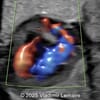

A 33-year-old nullipara with non-contributory medical history presented at 20 weeks, 6 days based on an early scan. Ultrasound revealed the following findings. There were no other apparent abnormalities. What is the most probable diagnosis?